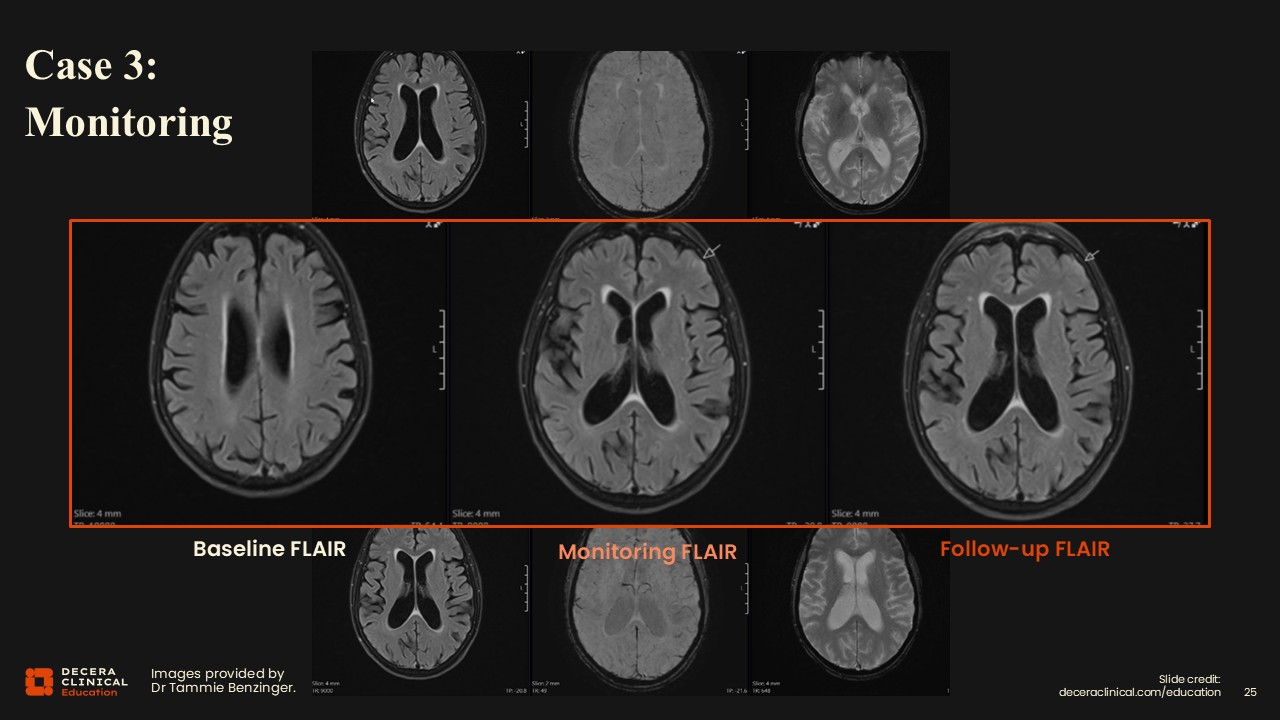

The patient developed siderosis at the same location which was identified at the next follow-up, prompting retrospective review and recognition of the subtle abnormality on the prior study. In this case, he had mild ARIA-E on the prior visit and then developed mild ARIA-H as well.

Radiologists may have cases where ARIA is identified in retrospect; it is important to communicate these findings to the clinical team about increased risk for future episodes. Because changes may be incremental over time, it is essential to review not only the most recent prior study but also the baseline examination, even when multiple time points are available.

If a prior report described the study as normal, that does not necessarily mean no abnormality was present; careful independent review remains essential. Radiologists should maintain a high index of suspicion; if ARIA is not being detected at a rate consistent with expectations (eg, approximately one case per five treated-patient MRIs), it is likely being under-recognized.